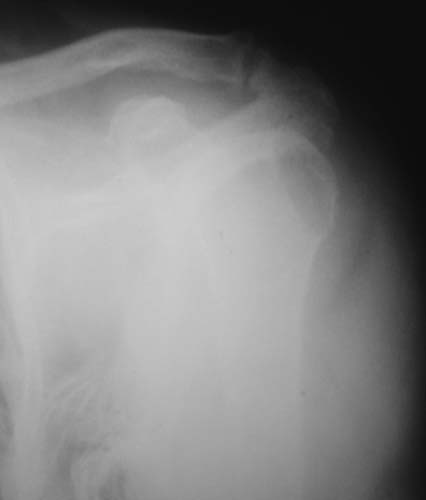

r1r2r3

Уважаемые коллеги!Женщина, 60 лет. 3 недели назад упала с упором на отведенную левую руку. Почувствовала боль в левом плечевом суставе. За помощью не обращалась. 2 недели "мази и припарки". Затем - рентгенограмма (r1 и r2), жалобы на боли,ограничение движений...

Активное отведение 80 гр., при пальпации - головка плечевой кости безболезненно вправляется и тут же самостоятельно вывихивается. Наложена косыночная иммобилизация, рентгенография (r3) и МРТ.В нашем диагностическом центре МРТ исследование плечевого сустава выполнено впервые, опыта у нас маловато :(.Вопросы: уточнение диагноза? какие исследования провести? тактика лечения?

К сожалению, нет! Сейчас попробую еще раз переснять снимки и МРТ. Возможно получится более качественно. Тем более, что упомянутый участок явно виден в прямой проекции рентгенограммы.

Как Вам известно, в некоторых случаях вывихи плеча сопровождаются разрывом ротаторной манжетки, отрывному перелому большого бугорка что приводит к потере наружной ротации и отведения плеча. На представленных рентгенограммах перелом не виден.

МРТ должен показать разрыв манжетки, но признаться я не большой эксперт по чтению МРТ сканов, хотя затемнение, отек мягких тканей по задней поверхности плеча видны Обычные рентгенограммы демонстрируют остеолизис в области большого бугорка.

1. На рентгене - нижний подвывих плеча и очаг остеолиза суставного бугорка с четкими контурами (вдавленный перелом на фоне остеопороза ? доброкачественная опухоль? аваскулярный некроз ? (хотя ни разу не слышал об аваскулярном некрозе плеча..)

Судя по снимкам, речь идTт о типичном случае Hill-Sachs Lesion. По этому поводу я позволю себе некоторый экскурс:

97 % всех вывихов плеча происходит по механизму комбинации отведения, разгибания и наружной ротации (А. Гринспан). В момент вывиха головка плеча ударяет о нижний край гленоида, что ведет к вдавленному или компрессионному перелому одной или обеих структур. Чаще всего, однако, повреждение возникает в задней латеральной области головки плечевой кости на переходе от головки к шейке. Этот диагноз можно выставить на основании рентгеновского снимка в переднезадней проекции с внутренней ротацией плеча. Несколько реже видно повреждение гленоида о передненижний перелом края. То, что мы называем Bankart Lesion. Это повреждение видно на ре. снимке в п.з. проекции при нейтральной позиции плеча. Разумеется хрящевые и мягкотканные повреждения (в смысле Банкарт) мы увидим лучше всего на ЯМР.

Учитывая описанную клинику, речь идTт о комбинации патологии. К сожалению, учитывая качество снимков NMR, я не могу провести достаточно точную верификацию состояния нижнего края гленоида, что впрочем, не меняет рекомендации. Для определения состояния РМ и дополнить исследование УЗИ мягких тканей плеча. В опытных руках достаточно информативное и дешевое исследование.